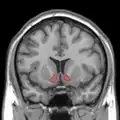

Approximate location of the nucleus accumbens in the brain